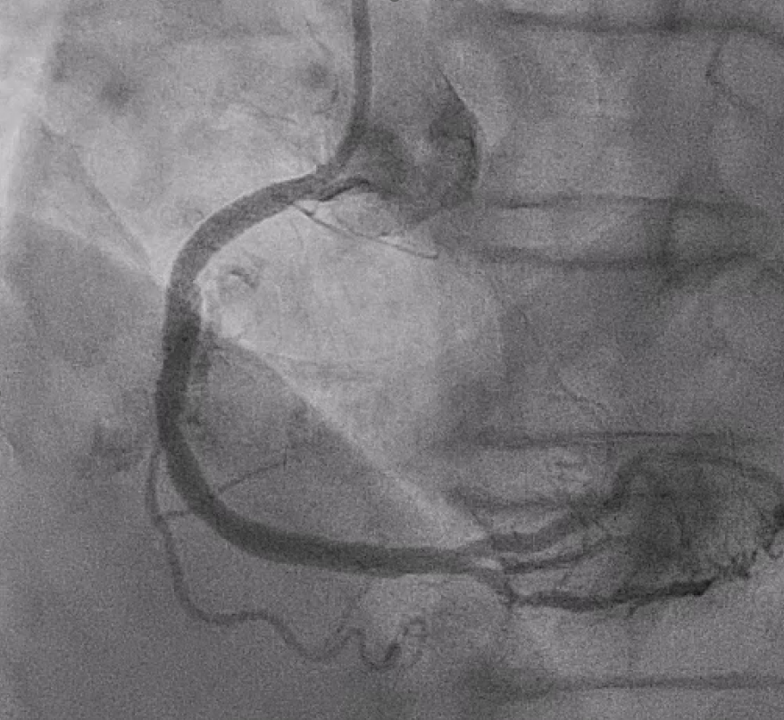

Coronary angiography showed a patent left main artery. The LAD had luminal irregularity with diffuse 70–90% stenosis from proximal to distal segments (Medina 1,0,1) involving the first diagonal branch and 70–80% tubular stenosis at the D1 ostium. The LCX showed prior stenting from proximal LCX to OM1 without in-stent restenosis and additional 50–60% stenosis at mid to distal segments. The RCA revealed diffuse eccentric 70–95% stenosis with severe calcification from proximal to distal segment.

Right distal radial artery was used for access with a 6 Fr JR 3.5 guiding catheter. Anticoagulation was given to keep ACT >250 seconds and dual antiplatelet therapy was continued. A Runthrough wire crossed the diffusely calcified RCA lesion from proximal to distal. Sequential predilation with 2.0–3.0 mm non-compliant balloons was performed to assess vessel compliance.IVUS showed heavy concentric calcification with a minimal lumen area of 3.3 mm©÷. Calcium modification was done using a 4.0 ¡¿ 12 mm intravascular lithotripsy balloon with a total of 70 pulses, achieving good luminal expansion. Two drug-eluting stents were then implanted: 3.5 ¡¿ 50 mm at mid–distal RCA and 4.0 ¡¿ 24 mm at proximal–mid RCA, followed by high-pressure post-dilation up to 20 atm.After optimization, angiography revealed Ellis class II–III perforation at mid RCA. A 7 Fr system with Guideliner support was used for bailout. A 3.5 ¡¿ 19 mm covered stent was deployed to seal the perforation, followed by additional dilation. Because of residual contrast leakage, another 3.5 ¡¿ 16 mm covered stent was placed at proximal RCA, achieving complete sealing.Final IVUS confirmed good stent expansion and apposition. Angiography showed less than 30% residual stenosis with TIMI 3 flow.